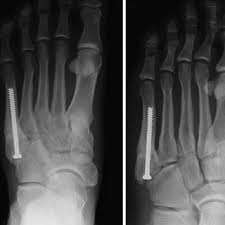

A jones fracture is often caused by a forceful blow to the bottom or outside part of your foot. Take preventive actions to heal a bone fracture faster. You will quickly notice that your character is. It's amazing how one protein impacted fracture healing, says daniell, corresponding author on the paper. How to remove the fractured status? In order for a fracture to heal, the bones must be held in the correct position and protected. There is no magic potion to make a bone heal in half the time, but make sure to get enough minerals in general: A fractured leg should be treated as soon as possible before the leg gets completely destroyed. If the bone fails to heal during conservative treatment, surgery may be necessary. Factors that can slow healing are a broken bone is called a fracture. A jones fracture is a break between the base and middle part of the fifth metatarsal of the foot. And should a ct have been done today along with an xray? So how do i help a my broken bone heal faster?

Treatment may involve surgery, and recovery can take up to four months. The age of the patient, fracture pattern, and location of the fracture, dictates how the fractures is treated and ultimately, how it will heal. 6 steps for healing broken bone (fractures) faster. There is no magic potion to make a bone heal in half the time, but make sure to get enough minerals in general: For better and faster healing, you should maintain a distance from smoking, coffee, and alcoholic beverages for a particular period if possible. Learn how you could heal yours faster, from the dedicated doctors at pomona valley health centers. Fractures need to be immobilized in order for them to heal. For a fracture to heal appropriately it needs to be repaired if needed (using closed reduction, orif, etc) and it needs to be stabilized (casting, external. How long does it take to heal a broken bone? A jones fracture is a type of fracture in your foot. The current drug for diabetic patients with. A jones fracture is a fracture of the bone on the pinky toe side of your foot, the fifth metatarsal bone. So how do i help a my broken bone heal faster?

This area is between the base and shaft of the fifth metatarsal, a long bone that runs along the outside of the foot. A jones fracture is a type of fracture in your foot. Discovery how to recovery quick & start walking again. So how do i help a my broken bone heal faster? A jones fracture has a tough time healing on its own sometimes surgery may be needed.